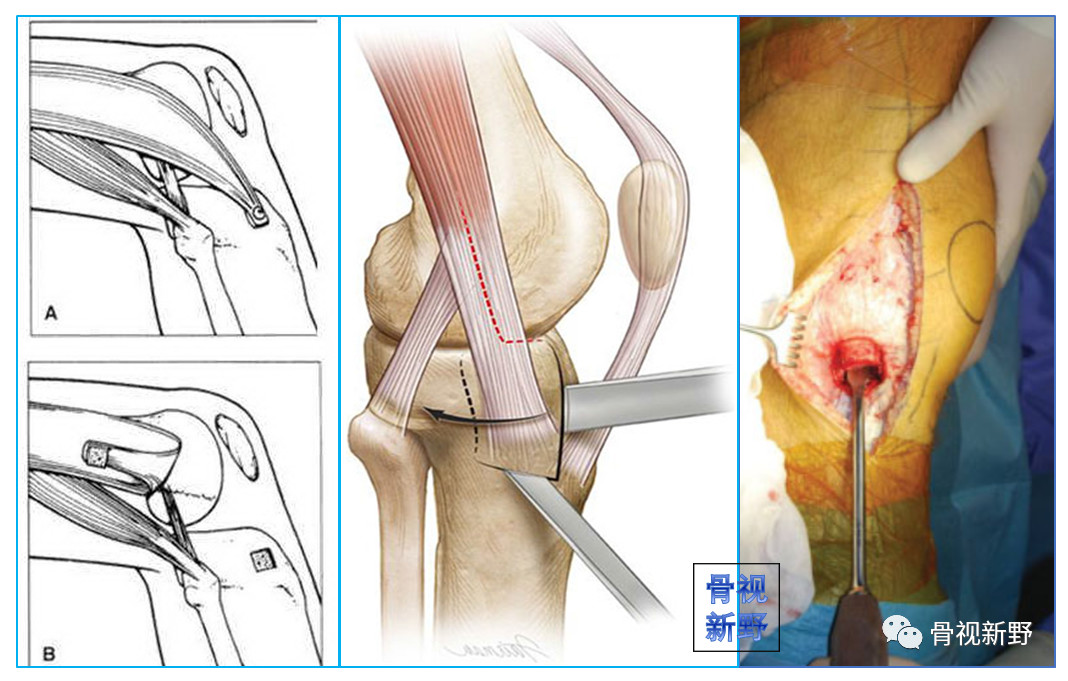

Gerdy结节截骨入路

入路同胫骨平台骨折的Gerdy结节截骨入路(如下示意图) 。平行于胫骨纵轴截取Gerdy结节骨块(大约1cm宽*2cm长*1cm厚)。然后将骨块连同其上附着的髂胫束向上翻转后能完全显露整个股骨外髁。

适用于Letenneur I、II、III型外髁Hoffa骨折,特别适合II型及外髁后部粉碎者。

该入路对外髁后部的显露较充分,可直视下由后向前打螺钉或完成支持钢板的固定。外髁Hoffa骨折固定完成后,再以带垫片的螺钉通过预先钻孔将Gerdy结节原位钉回(截骨前预钻孔!)。